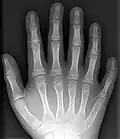

Polidaktylia (polydaktylia) (gr. polýs – wiele, mnogi; dáktylos – palec) – wada wrodzona polegająca na obecności dodatkowego palca bądź palców, najczęściej I lub V.

Dodatkowe palce mogą być cechą zaburzeń chromosomowych (np. zespół Pataua), zaburzeń monogenowych autosomalnie dominujących lub o etiologii nieznanej. Polidaktylia może być wadą izolowaną lub stanowić część obrazu klinicznego wielu zespołów wad wrodzonych. Jest to najczęściej występująca wada kończyn górnych. Niekiedy występuje łącznie z palcozrostem (syndaktylia)[1].